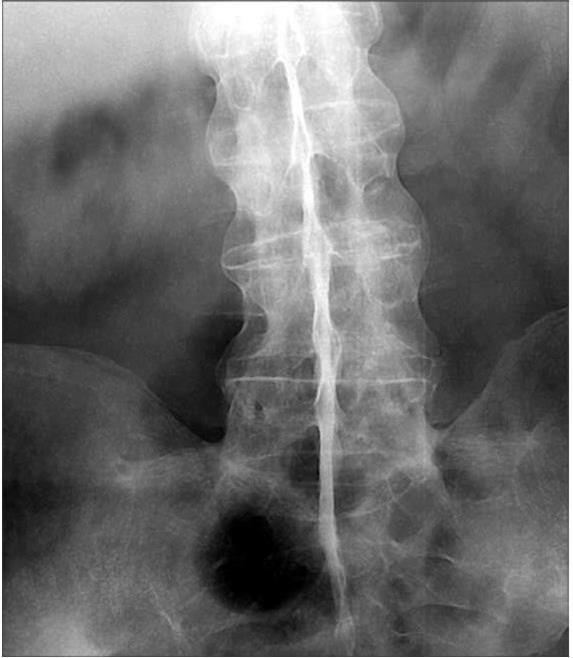

Центральная форма АС — самая частая, в пожилом возрасте отмечена нами у 40 % пациентов. Она, как правило, осложнена грудным, поясничным радикулитом и вертебробазилярной недостаточностью. При сочетании АС с сахарным диабетом в ряде случаев диагностируют полирадикулоневрит. Рентгенологически выявляют анкилоз крестцово-подвздошного сочленения, чаще двусторонний, деструктивный, и склеротические изменения в межпозвоночных и реберно-позвоночных суставах, их анкилоз. Наряду с остеопорозом позвонков, атрофией их поперечных отростков, характерно окостенение межпозвоночных фиброзных колец, передней и боковых позвоночных связок. Все это придает позвоночному столбу форму бамбукового ствола (рис. 20). Вместе с тем у пациентов пожилого возраста при рентгенографии в 50 % случаев можно обнаружить проявления спондилеза, остеохондроза.

Рис. 20. Рентгенограмма нижнегрудного, поясничного отделов позвоночника и крестцово-подвздошного сочленения больного АС. Центральная форма анкилозирующего спондилоартрита

Резко выраженный остеопороз. Анкилоз крестцово-подвздошных сочленений, окостенение передней и боковых связок — «бамбуковый ствол»